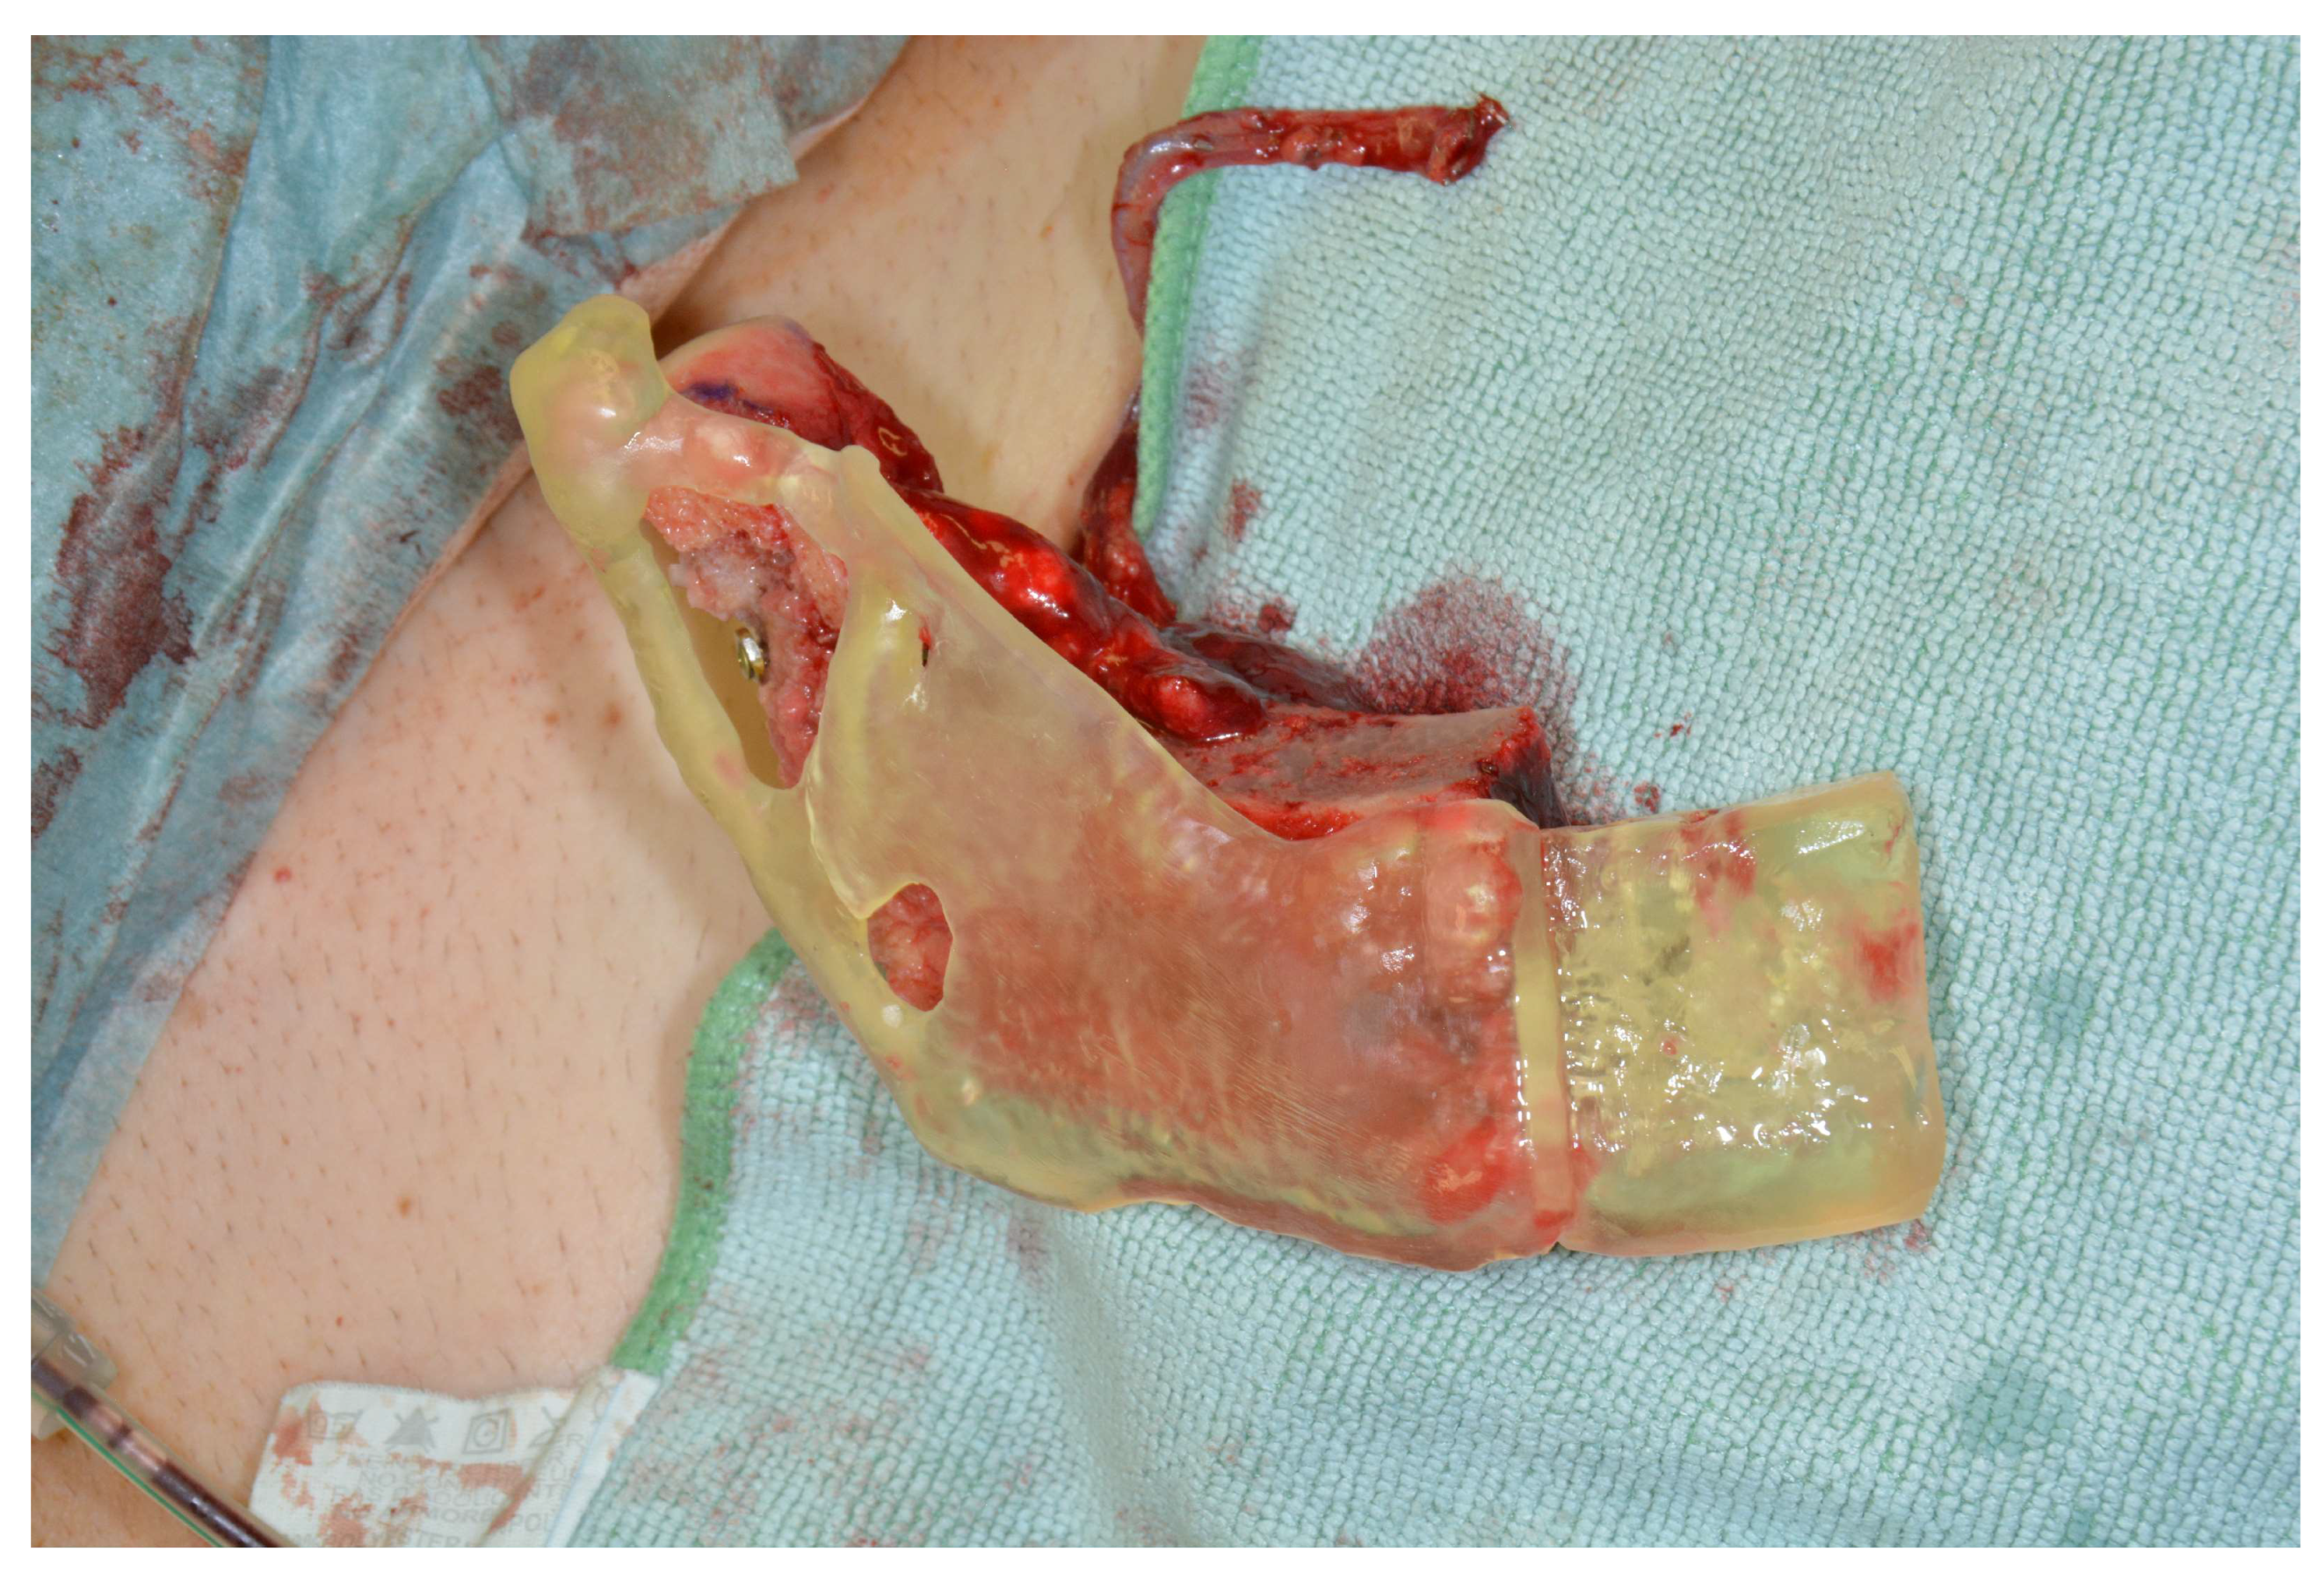

2.2. Surgical Procedure

| Patient 3 | 17 | f | Goldenhar syndrome | 80 | Rarely light pain | Cannot be assessed | Not applicable due to skin transfer | Cannot be assessed | 20 mm | 35 mm | 70 | Yes |

| Patient 4 | 51 | m | Adenocarcinoma of the parotid gland | 80 | Joint noise, no pain | 8 | Not applicable due to skin transfer | Nearly no complaint | 40 mm | 35 mm | 24 | Yes |